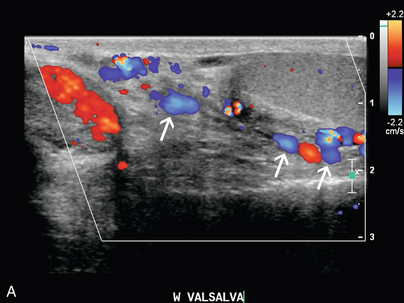

Формирование варикоцеле

Варикоцеле — это расширение гроздьевидного венозного сплетения, наблюдаемое при ультразвуковом исследовании яичек, которое чаще встречается слева из-за анатомических факторов угла вхождения гонадной вены в левую почечную вену и возможности сдавления левой почечной вены СМА. . Первичный тип варикоцеле связан с недостаточностью клапанов, а вторичный тип связан с повышением венозного давления из-за затруднения венозного оттока. Изолированное правостороннее варикоцеле встречается редко и требует дальнейшей оценки правой забрюшинной области и почки для исключения образования в правой почке или аденопатии, сдавливающей венозный отток. Диагноз варикоцеле ставится при ультразвуковом исследовании яичек, когда вены в области семенного канатика расширены до диаметра более 2–3 мм ( рис. 9-24 ). Редко варикозное расширение вен может располагаться интратестикулярно. В некоторых случаях цветная допплерография расширенных вен может выявить внутрипросветный тромб. Реверс венозного кровотока в состоянии покоя с усилением обратного кровотока во время Вальсальвы указывает на диагноз, но у некоторых пациентов может наблюдаться только реверс во время Вальсальвы. Методы, используемые для улучшения выявления варикоцеле, включают вальсальву или положение стоя. Как отмечалось ранее, недавнее исследование Karazincir et al. показали, что частота ретроаортального поражения левой почечной вены была значительно выше у пациентов с варикоцеле по сравнению с контрольной группой.

РИСУНОК 9-24 Варикоцеле. (А) Цветная допплерография показывает расширение и увеличение кровотока в сосудах (стрелки) семенного канатика и мошонки во время Вальсальвы диаметром более 3 мм. При пограничных результатах положение пациента стоя может усилить эти результаты. (B) КТ у того же пациента показывает ретроаортальную левую почечную вену (черная стрелка).